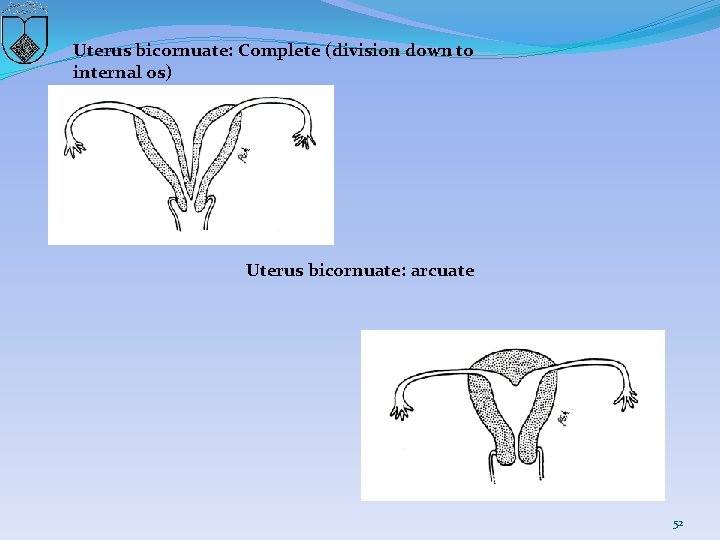

Lateral fusion defects �Septate/arcuate uterus �Unicornuate uterus �Bicornuate uterus �Uterine didelphys 50

Uterus bicornuate: Complete (division down to internal os) Uterus bicornuate: arcuate 52